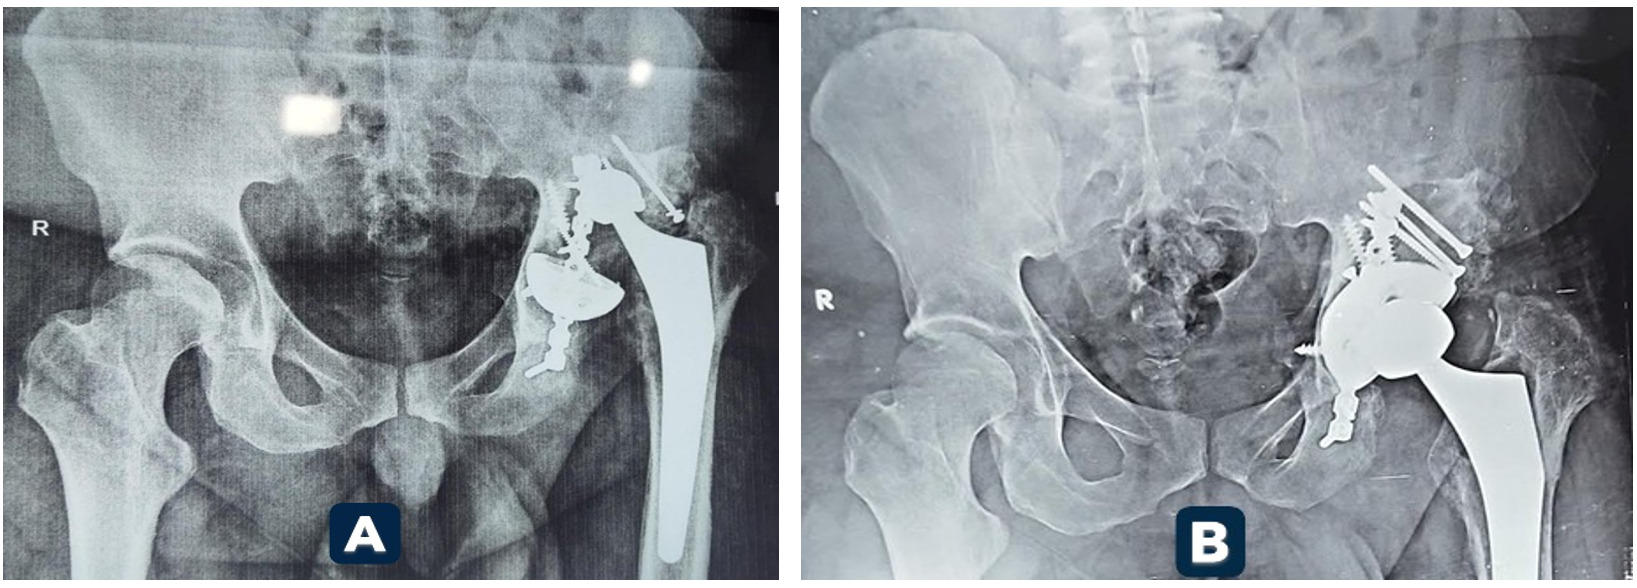

At final follow-up, 95.5% of Mega Cup reconstructions remained in situ, with no evidence of loosening. Kaplan–Meier analysis demonstrated a 95% cumulative survival rate at 5 years. Radiographic assessment confirmed stable fixation in 90.9% of hips. Graft incorporation was observed in 88.9% of cases. (Figures 1 and 2 illustrate radiographic outcomes.)

Kaplan–Meier analysis revealed a 95% 5-year survivorship rate, consistent with mid-term outcomes reported by Wang3 (>90%) and aligning with the favorable long-term results documented by Oommen4 at 10–14 years. Radiographic stability was achieved in 90.9% of hips, and graft incorporation was observed in 88.9% of cases. These findings parallel outcomes reported for porous titanium and tantalum constructs, reinforcing the biological advantage of highly porous shells in promoting osseointegration.5–8